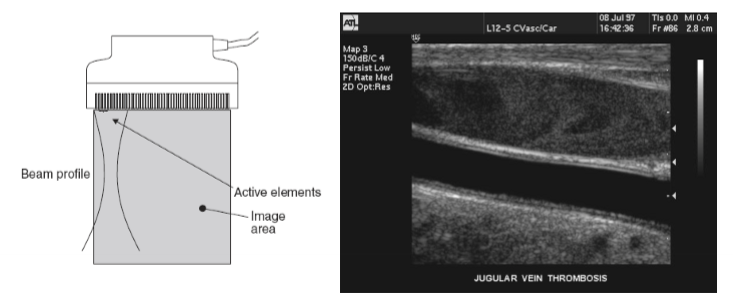

linear arrays:

elements are in a straight line and are fired as a group

beam electronically focused

used in musculoskeletal and vascular imaging